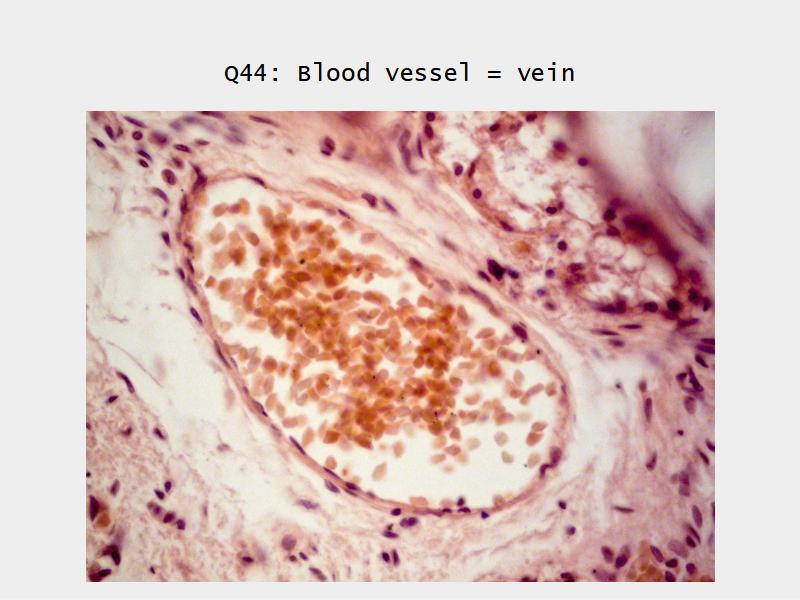

The cardiovascular system needs to be connected to the respiratory system.Path of O2 and CO2

- List complete

- With layers

- And cells

- And function of each